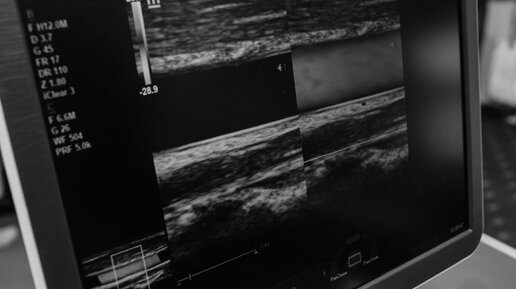

Допплеровская оценка нарушений структуры артериального потока